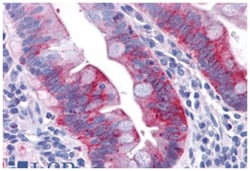

GPR31 Rabbit anti-Human, Polyclonal Antibody, Abnova™

Rabbit polyclonal antibody raised against synthetic peptide of GPR31.

| Immunohistochemistry (Formalin/PFA-fixed paraffin-embedded sections) (2-4 ug/mL) The optimal working dilution should be determined by the end user. | |

| A synthetic peptide corresponding to 19 amino acids at extracellular domain of human GPR31. | |